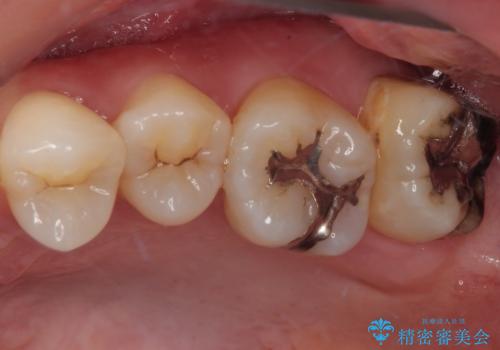

- 元々むし歯があったものの、処置が困難とのことでしたが、矯正治療を終えたので処置をしたいとのことで来院された患者様です。

左右ともに最後臼歯が頬側に顕著に突出しており、むし歯になってしまったことが想像されました。

矯正治療により処置が可能な位置に歯が移動したため、オールセラミッククラウンにて補綴治療を行うこととしました。

歯列が移動したとはいえ、左右ともに後方傾斜しており、むし歯の除去、形成(形を整える)、型取りの全てが非常に困難な処置となりました。